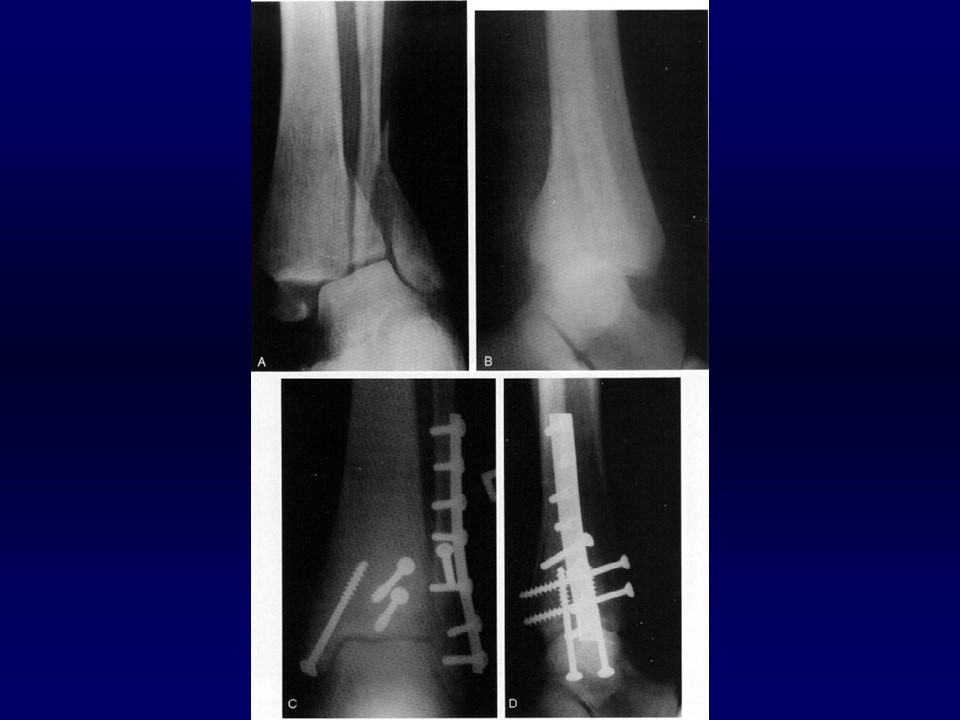

踝关节骨折的治疗PPT

Ramsey and Hamilton: 1 毫米的外移, 胫距关节接触面积将减少42%